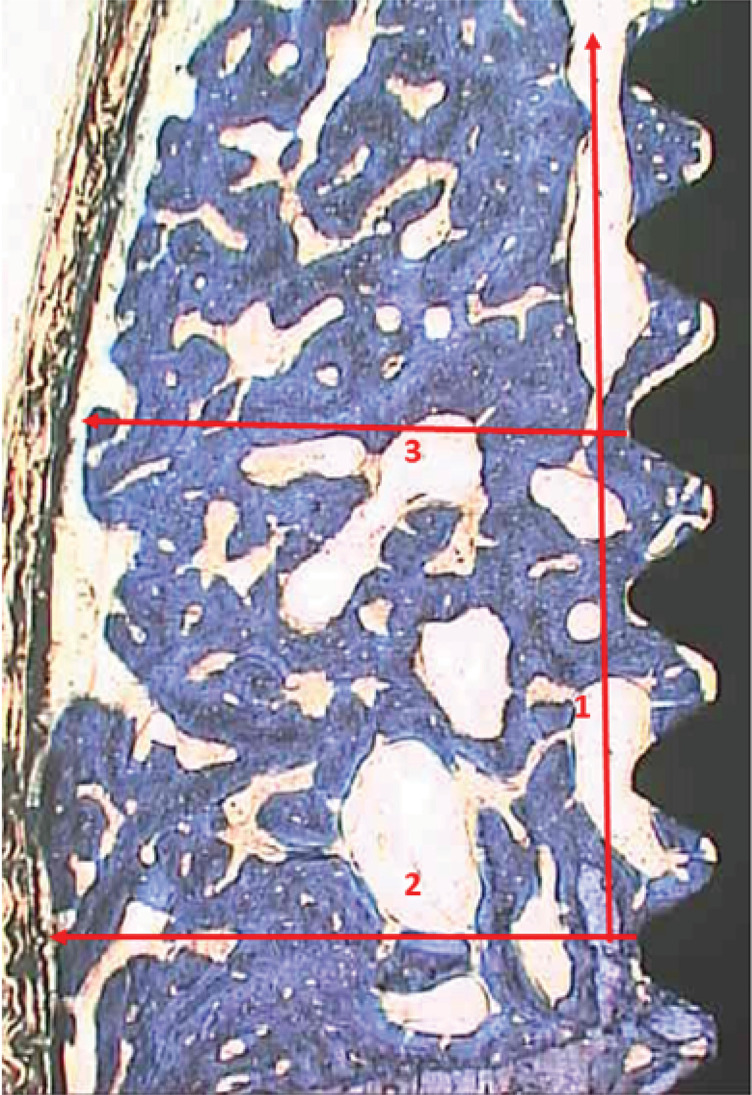

本研究旨在从组织形态学角度评价引导骨再生(GBR)和两种种植体表面对钛种植体周围裂隙缺损新生骨厚度和高度的影响。从10只成年杂种狗身上拔出3颗前磨牙和第一颗双侧磨牙,用北卡罗来纳大学牙周探针确定40个高5 mm、宽4 mm的颊骨裂缝的尺寸。将40个种植体随机分为四组:氧化种植体表面(OIS, n = 10)、车削/加工种植体表面(TIS, n = 10)、OIS + GBR (n = 10)和TIS + GBR (n = 10)。3个月后,对狗实施安乐死,并对含有植入物和相邻骨的块进行非脱钙组织学分析。统计学分析采用双因素方差分析和Pearson相关分析(p = 0.05)。结果显示,GBR对新生骨的垂直(高度)和水平(厚度)尺寸均有显著影响(p < 0.001)。在缺损底部新形成骨的厚度和高度之间,以及缺损底部骨的厚度和缺损中心区域新形成骨的厚度之间,观察到很强的正相关。种植体表面类型与骨形成无显著相关性。骨再生发生在垂直和水平方向,无论种植体表面类型(氧化或翻转)如何,gbr处理组的骨生长都更大。

This study aimed to histomorphometrically evaluate the effect of guided bone regeneration (GBR) and two implant surfaces on the thickness and height of newly formed bone in dehiscence defects around titanium implants. Three premolars and the first bilateral molar were extracted from ten adult mongrel dogs, and 40 buccal bone dehiscences measuring 5 mm in height and 4 mm in width were created using a University of North Carolina (UNC) periodontal probe to confirm the dimensions. Forty implants were randomly assigned to one of four groups: oxidized implant surfaces (OIS, n = 10), turned/machined implant surfaces (TIS, n = 10), OIS + GBR (n = 10), and TIS + GBR (n = 10). After 3 months, the dogs were euthanized, and the blocks containing the implants and adjacent bone were processed for non-decalcified histological analysis. Statistical analysis was performed using two-way ANOVA and the Pearson correlation (p = 0.05). The results showed that GBR significantly influenced both the vertical (height) and horizontal (thickness) dimensions of the newly formed bone (p < 0.001). Strong positive correlations were observed between the thickness and height of newly formed bone at the base of the defect, as well as between the thickness of the bone at the base of the defect and the thickness of newly formed bone in the central region of the defect. No significant correlations were found between implant surface type and bone formation. Bone regeneration occurred in both the vertical and horizontal directions, with greater bone growth in GBR-treated groups, irrespective of implant surface type (oxidized or turned).